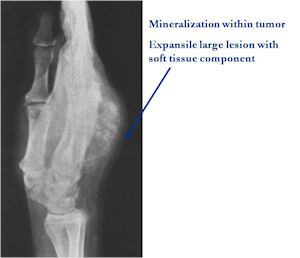

Radiographic Presentation

Plain X-rays:

- Geographic, circumscribed lesion usually around 5cm in size.

- There may be expansion of bone, cortical thinning and cortical breakthrough. A soft tissue mass may accompany this lesion but the soft tissue component is usually contained by the periosteum.

- The periosteum remains intact around the soft tissue component. Might need a CT scan to detect the subtle calcification (Egg Shell Rim of Calcification) associated with an intact periosteal reaction

- The lesion may be entirely radiolucent but usually shows some degree of mineralization. Mineralization may appear stippled like cartilage but do not see chondroid pathologically. Mineralization is sometimes better detected on a CT scan rather than an x-ray.

- Usually less surrounding sclerosis than an osteoid osteoma.

- Arise from the Diaphysis (75%) more commonly than Metaphyseal (25%)

- 4 cm to 6 cm in size